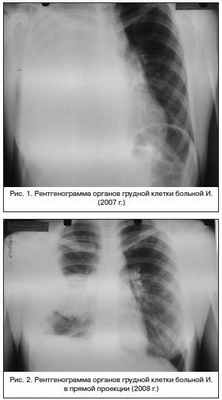

Также известно, что в 2007 г. у пациентки при плановом флюорографическом исследовании было заподозрено образование переднего средостения, по поводу чего проводилось обследование в онкологическом стационаре, где была выполнена трансторакальная пункция, диагноз был снят. В течение 1 нед. после пункции у пациентки появились жалобы на слабость, лихорадку до 39°С, одышку, боли в правой половине грудной клетки, малопродуктивный кашель. Была госпитализирована, получила курс лечения в стационаре по поводу тотальной эмпиемы плевры справа, который включал в себя стандартную консервативную терапию и дренирование правой плевральной полости в течение 50 дней. Выписана без дренажа в удовлетворительном состоянии, при рентгенологическом исследовании перед выпиской патологии органов средостения и правой половины грудной клетки не определялось. В 2008 г. пациентка поступила повторно с клинико-рентгенологической картиной распространенной эмпиемы плевры справа, вновь были проведены дренирование правой плевральной полости и курс консервативной терапии с хорошим клиническим и рентгенологическим эффектом. В течение 2-х лет жалоб со стороны бронхолегочной системы у пациентки не было. Больной представлены данные рентгенологического исследования грудной клетки от 2007 г. (рис. 1). Заключение: тотальная простая эмпиема плевры справа.

Данные рентгенологического исследования от 2008 г. представлены на рисунках 2, 3. Заключение: ограниченная простая эмпиема плевры справа.